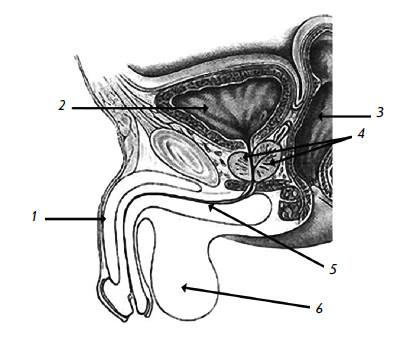

Мужской мочеиспускательный канал (рис. 3) длинный и узкий (длиной 20–40 см, шириной около 8 мм). Ниже мочевого пузыря находится предстательная железа (простата). Она со всех сторон охватывает начальную часть мочеиспускательного канала. Выводные протоки предстательной железы открываются в мочеиспускательный канал. Одной из функций простаты является выделение секрета, который обладает антимикробным действием и препятствует инфицированию мочевых путей.

Рис. 3. Мужской таз

1 – половой член; 2 – мочевой пузырь; 3 – прямая кишка; 4 – предстательная железа; 5 – мочеиспускательный канал; 6 – мошонка и яички